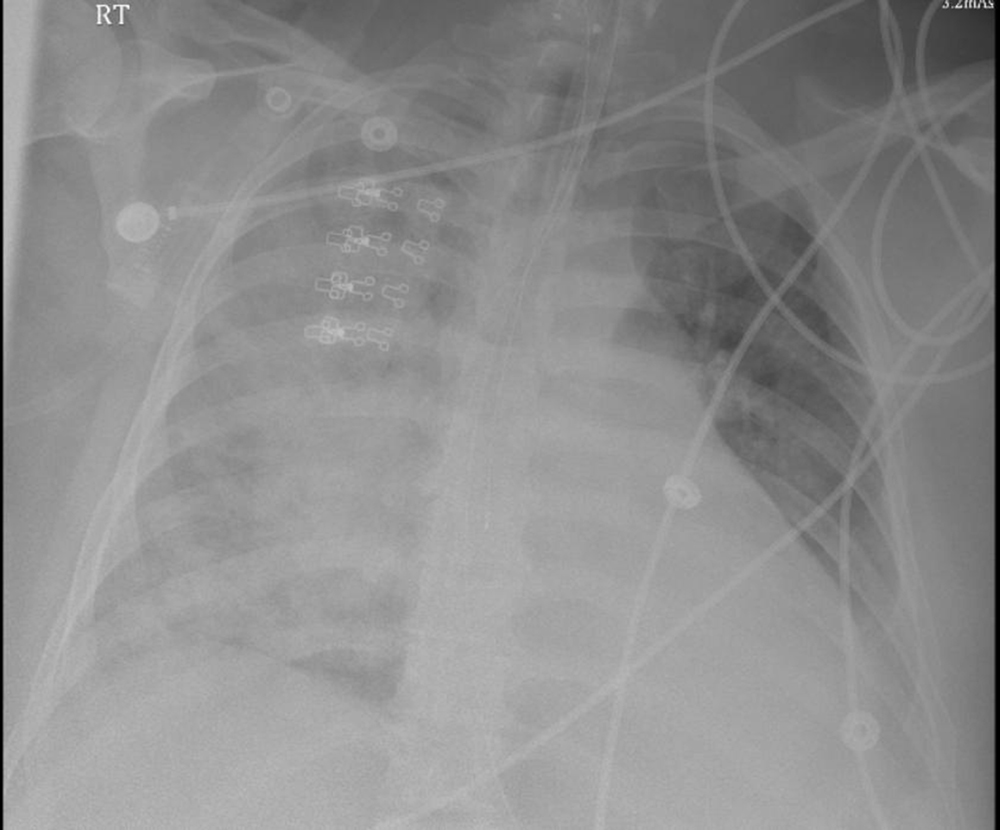

Blood work on admission showed white cell count 8200 cells/µL, hemoglobin 11gm/dL, platelets 193000/µL, and procalcitonin 0.730 ng/mL; her prothrombin time was 12.3 seconds (INR = 1.18). During the first three days of admission, her hemoglobin count dropped to 8.8 gm/dL. She had no sign of active bleeding. Her electrocardiogram showed a sinus rhythm and incomplete right bundle branch block with non-specific ST-T wave changes in anterior leads. Chest x-ray on admission showed extensive opacity in the right lung and a dense opacity in the left lung base. The next day the chest x-ray had worsened with bilateral opacities (Figure 1). Chest computed tomography scan showed bilateral pleural effusions with bilateral pulmonary infiltrates (Figure 2). The patient was initially placed on empiric antibiotics for hospital-acquired pneumonia; however, no clinical improvement was noted over 48 hours, and antibiotics were discontinued.

Figure 1

Figure 1. Portable chest x-ray revealing dense alveolar infiltrates, especially in the right lung.